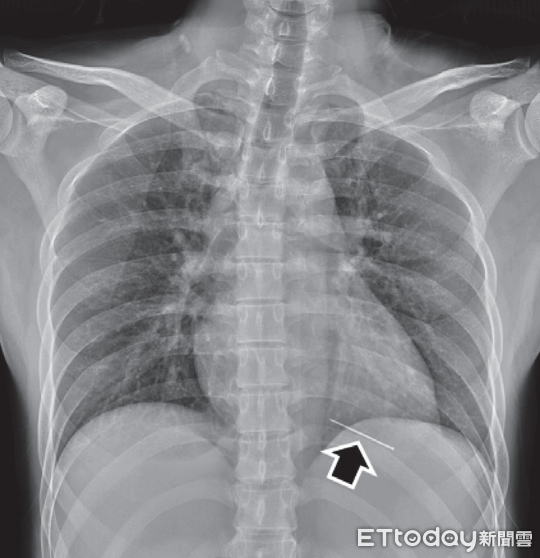

▲男子遭釘槍射入左心室,從X光片可見有異物緊臨心臟 。(圖/賴雨濃醫師提供,下同)

「一箭穿心」發生在真實世界竟能保命。一名37歲男性遭釘槍射入左心室,急診醫師最初僅在左胸看到小傷口,X光片則有異物陰影,以「重點式照護超音波」一掃,才發現異物已插入左心室,隨即緊急手術、取出釘子;醫師說,左心室穿刺傷罕見能活著到醫院,救回一命更少,病人真的命大。

對此幸運案例,賴雨濃回憶,患者當時送來已恢復意識,但持續躁動且多汗,只能模糊交代傷勢原因;在初步檢查中,發現他的左胸乳頭內側有微小穿刺傷,不過出血極少,也查無異物,胸部X光則顯示心臟左側有陰影,急診團隊隨即在床邊使用重點式照護超音波(POCUS)以進一步確認異物位置。